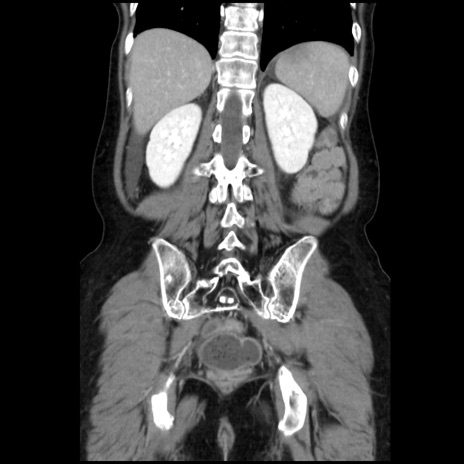

症例32(冠状断像)

【症例】40歳代 女性

【主訴】上腹部痛、嘔気・嘔吐

【現病歴】約9時間前頃から急に上腹部痛、嘔気、嘔吐が出現。改善しないため救急要請。

【既往歴】子宮頚癌(広汎子宮全摘術、放射線療法)、腸閉塞

【身体所見】腹部:平坦、軟、腸雑音亢進、上腹部を中心に腹部全体に圧痛あり。

【データ】WBC 8400、CRP 0.03